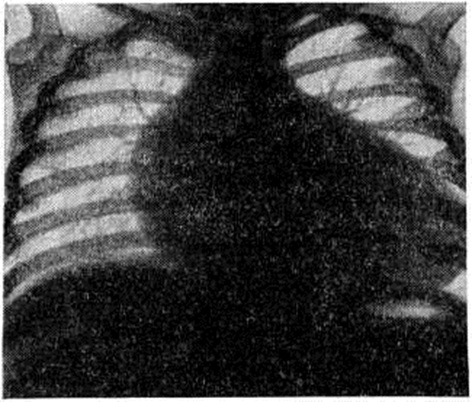

При рентгенологическое исследовании выявляется нормальный или несколько усиленный но венозному руслу лёгочный рисунок, кардиомегалия, шаровидная или овоидная форма сердца (рисунок). Пульсация снижена. Кардиоторакальный индекс — отношение поперечного размера сердца к поперечному размеру грудной клетки на уровне диафрагмы, выраженное в процентах,— составляет у большинства больных 70—75% (в норме у детей 50%). На ЭКГ (смотри полный свод знаний: Электрокардиография) — нормальное положение электрической оси сердца, высокий вольтаж зубцов, ригидный частый ритм, признаки гипертрофии миокарда левого предсердия и желудочка, глубокие отрицательные или сглаженные зубцы Т в отведениях V4-6, опущение сегмента S Т ниже изолинии. Нарушения ритма и проводимости не характерны для Фиброэластоз субэндокардиальный, однако возможно появление экстр асистолии (смотри полный свод знаний), пароксизмальной тахикардии (смотри полный свод знаний), внутрижелудочковой и атриовентрикулярной блокад (смотри полный свод знаний: Блокада сердца). При фонокардиографическом исследовании (смотри полный свод знаний: Фонокардиография) выявляется значительное снижение амплитуды I тона и систолический шум лентовидной формы в области верхушки сердца.

Рис

Рентгенограмма органе к грудной клетки (прямая проекция) больного субэндокардиальным фиброэластозом: лёгочный рисунок не изменён; сердце увеличено, овоидной формы.